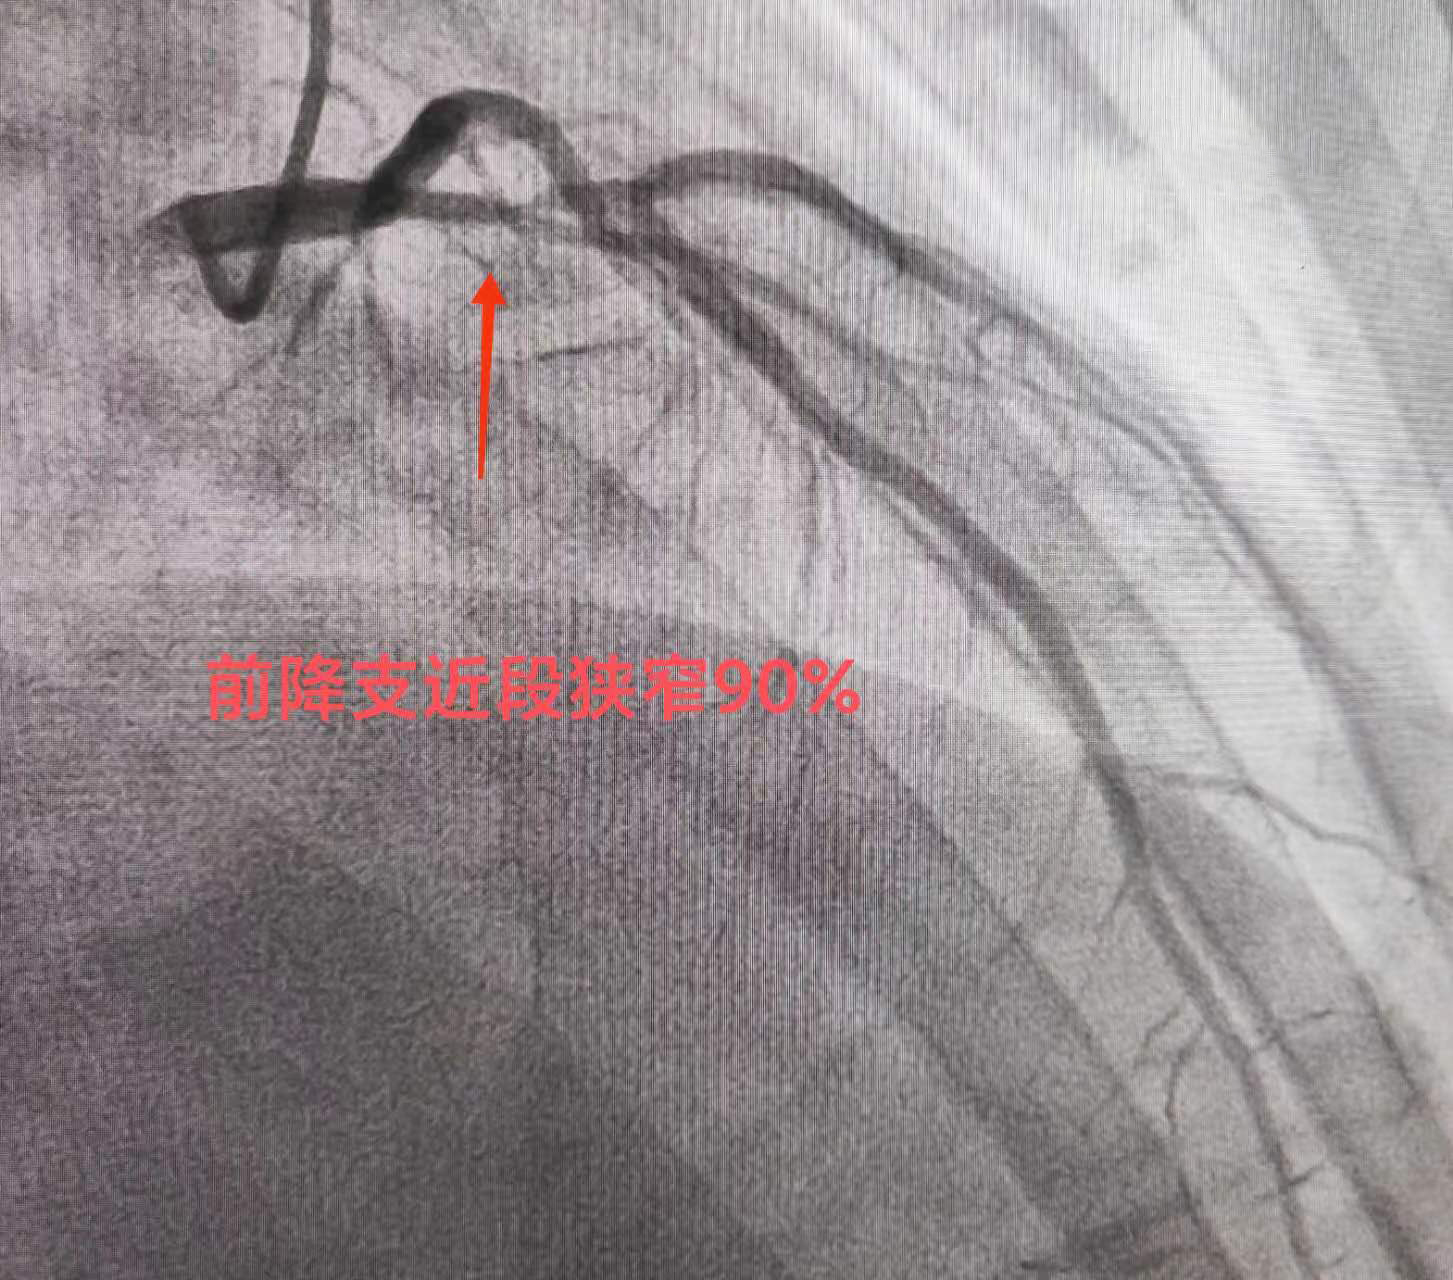

导管室内,秉承患者生命至上的原则,医院迅速安排当日前来坐诊的河北以岭医院心血管病科洪衡主任医师(河北省急救医学会胸痛专业委员会主委)及介入团队为其行冠脉造影。造影显示:前降支——开口至近段30-90%节段性狭窄。在取得家属的同意下行冠脉支架植入术,于前降支植入一枚支架。术毕,患者胸痛明显缓解,安返病房,给予密切监护。